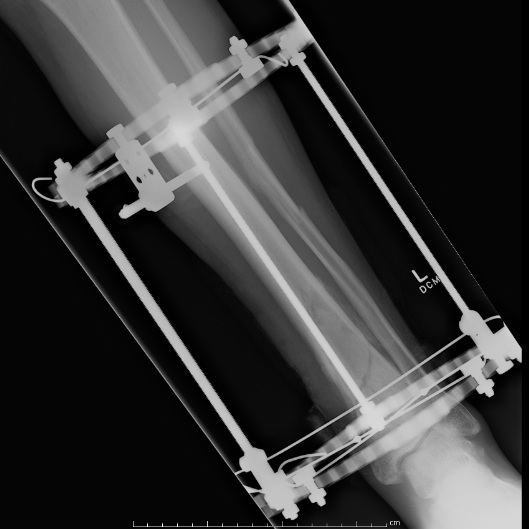

Temporary External fixation

Indications

- significant swelling

- significant displacement / non controlled in cast

- significant wounds, need for soft tissue coverage

Technique

- two pins proximal tibia

- trans-calcaneal pin

AO Trauma Ankle Bridging Delta Frame